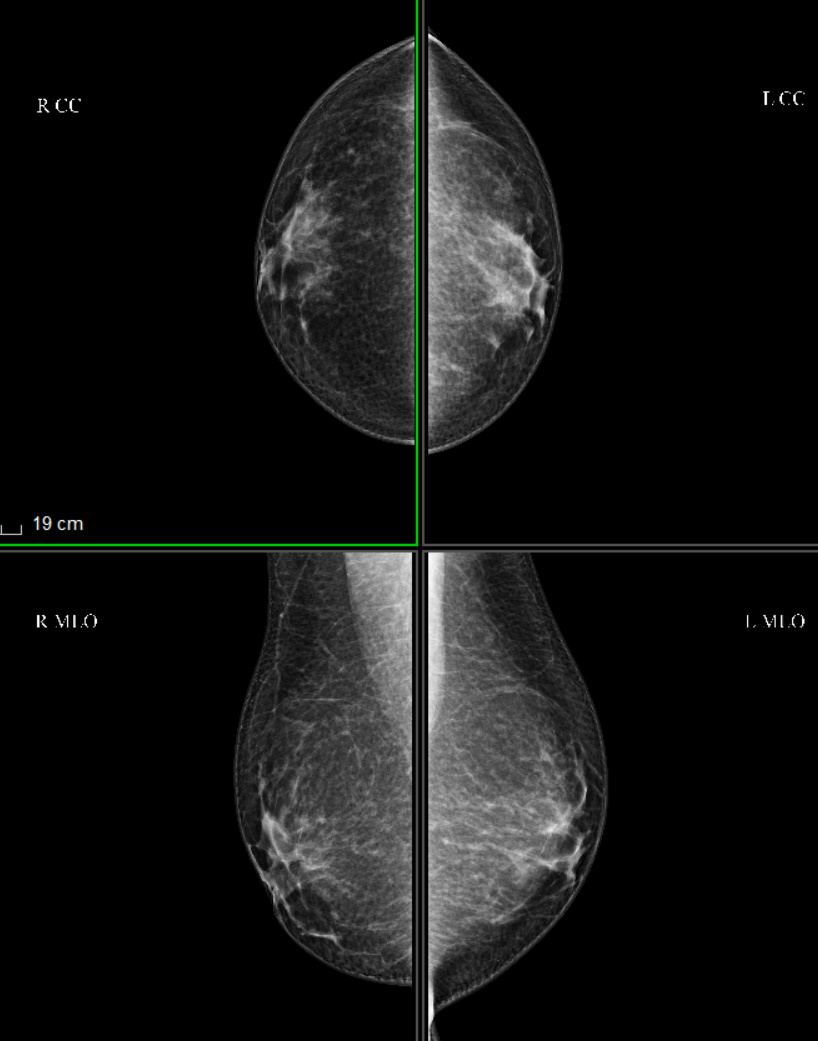

1.乳腺钼靶(X线摄影):国际金标准,精准筛查。

乳腺钼靶作为乳腺癌筛查的国际金标准,对微小钙化灶具有极高的敏感性。对于40岁以上的女性来说,每年进行一次乳腺钼靶检查是非常必要的。乳腺钼靶检查安全高效,辐射剂量低,对身体安全不构成威胁,整个检查过程仅需几分钟,就能对乳腺疾病作出初步诊断。

乳腺钼靶正常乳腺的图像